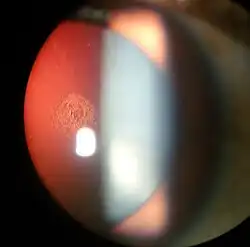

Magnified view of a cataract seen on examination with a slit lamp | |